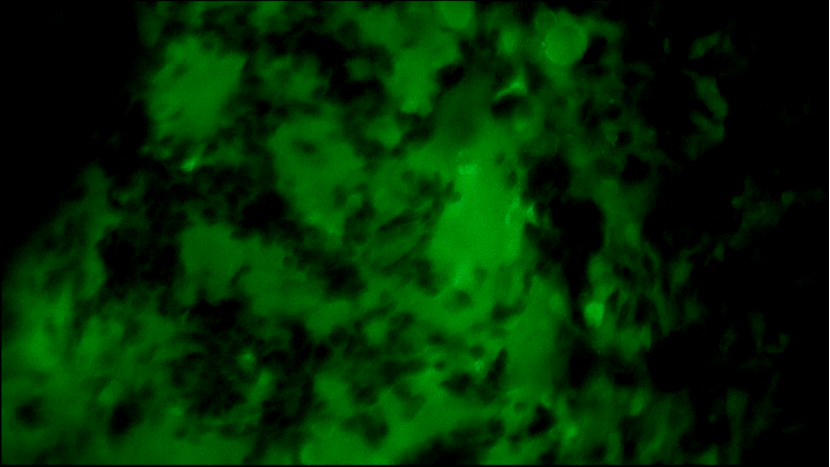

術(shù)中EndoSCell?細(xì)胞圖像如下:

右乳腫物:細(xì)胞核體積較大,大大小小形態(tài)不一,且細(xì)胞核密度高。